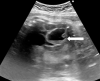

Figure 3

un aspect échographique stable de l´image intra-abdominale

Figure 4

formation kystique au niveau de l´hypochondre gauche, de 45 mm x 19 mm, multi cloisonnée, pouvant cadrer avec une duplication digestive iléale non compliquée